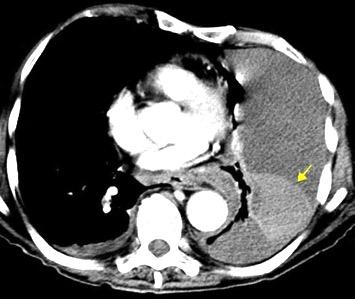

En el hemotórax, los elementos formes de la sangre tienden a depositarse en la parte más declive

Polireddy K et al. Blunt thoracic trauma: role of chest radiography and comparison with CT findings and literature review . Emerg Radiol 2022.

Neumo-Hemotórax

Sin fracturas: 6,7%

1-2 fracturas: 24,9% + de 3 fracturas:81,4%

Colección pleural

Hemorrágica.30-70 UH

Extravasación iv con sangrado activo.>90 UH “Simpático”..<15 UH

Urogénico…< 15 UH